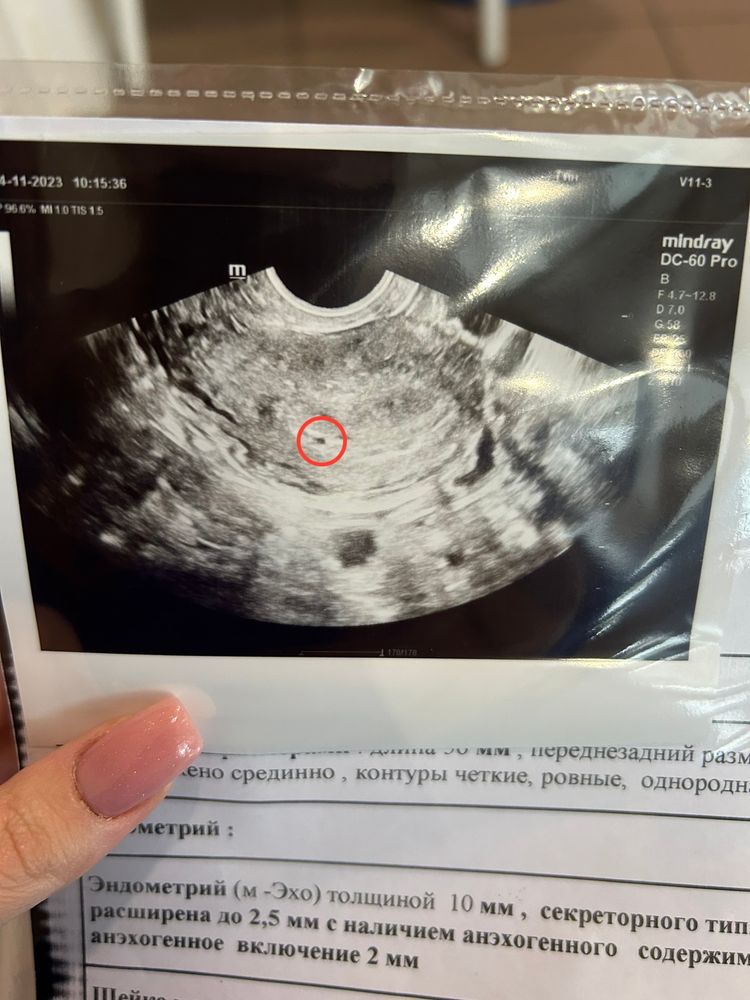

Узи в 4+6 недель

Изображение

Сдавала хгч в динамике 17.11 - 114; 19.11 - 336; 23.11 - 2200. Прогик свой замечательный, но все равно на поддержке, так как была мазня за день до задержки.